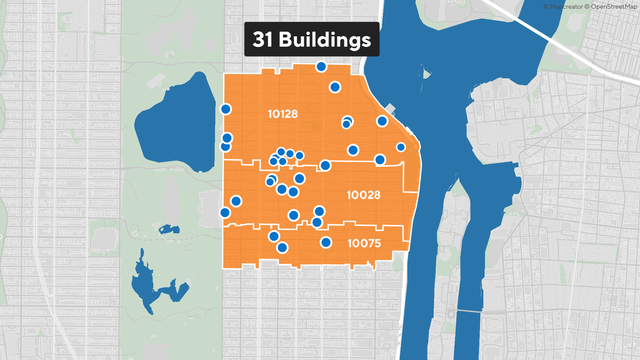

New York City has tested about 150 cooling towers for Legionella bacteria and detected it in at least one on Manhattan's Upper East side.

Thirty-one people who were hospitalized with Legionnaires' disease on the Upper East Side have been discharged, New York City health officials said Saturday.

New York City's Health Department says it identified 31 buildings where Legionella bacteria has been detected on the Upper East Side.

New York City has tested about 150 cooling towers for Legionella bacteria and detected it in at least one on Manhattan's Upper East side.

Over two dozen people sickened by Legionnaires' disease on the Upper East Side are now out of the hospital, New York City health officials say.